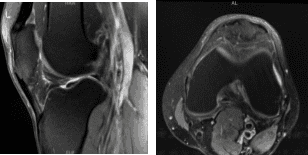

MRI-3T Rodilla Izquierda sin contraste

La paciente presentó resultados de resonancia magnética que mostraron cuádriceps insertional leves a moderados y tendinosis patuliana proximal. Hay un espolón prominente a lo largo del polo inferior de la rótula sin un fragmento osífico separado ni edema de médula ósea circundante, indicativo de una lesión previa por tracción.

No hay desgarro meniscal ni lesión de ligamentos. El cartílago se conserva. En la rodilla derecha, los resultados de la radiografía han mostrado desgarro superficial bajo la parte inferior en la unión del cuerno posterior/cuerpo del menisco medial y deshilachamiento inferior del cuerno posterior.

Cuádriceps leve y tendinosis rotuliana, sin desgarro. Bursitis prepateliana leve y edema moderado de tejidos blandos circundantes. Hablamos del tratamiento con el paciente. El paciente había probado fisioterapia en el pasado.